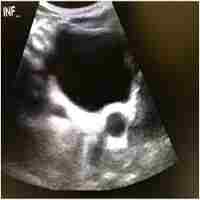

Primary bilateral non-refluxing non-obstructive megaureter in an adult: An extremely rare case

| Abstract | Refluksif ve obstruktif olmayan megaurter genellikle yeni doganlarda teshis edilir. Yetiskinlerde cok nadirdir. Bu olgu sunumunda makroskopik hematuri ile basvuran 45 yasindaki bir erkek hasta sunuldu. Klinik degerlendirmelerden sonra primer refluksif ve obstruktif olmayan megaureter teshisi kondu. Buna ek olarak, bu cok ender vaka esliginde mevcut literaturu gozden gecirdik. |